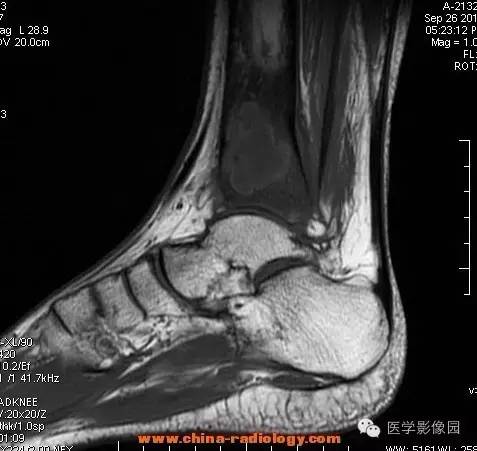

影像学表现:胫骨中下段干骺端不未规则形长T1长T2信号,T2WI见不完整环形稍低信号影,T2脂肪抑制低信号更明显,并见胫骨下段及踝关节后外侧软组织呈弥漫稍高信号,增强明显不均匀强化,增强见低信号环内有环形强化影。

影像学表现:表现为长骨干骺端有椭圆形密度减低区,边缘有清晰的骨质硬化,病变与邻近正常骨髓腔境界清楚。MRI上T1WI呈低信号,少数呈等信号,T2WI多为混杂高信号,增强扫描可见环状强化,强化的脓肿壁薄而均匀。